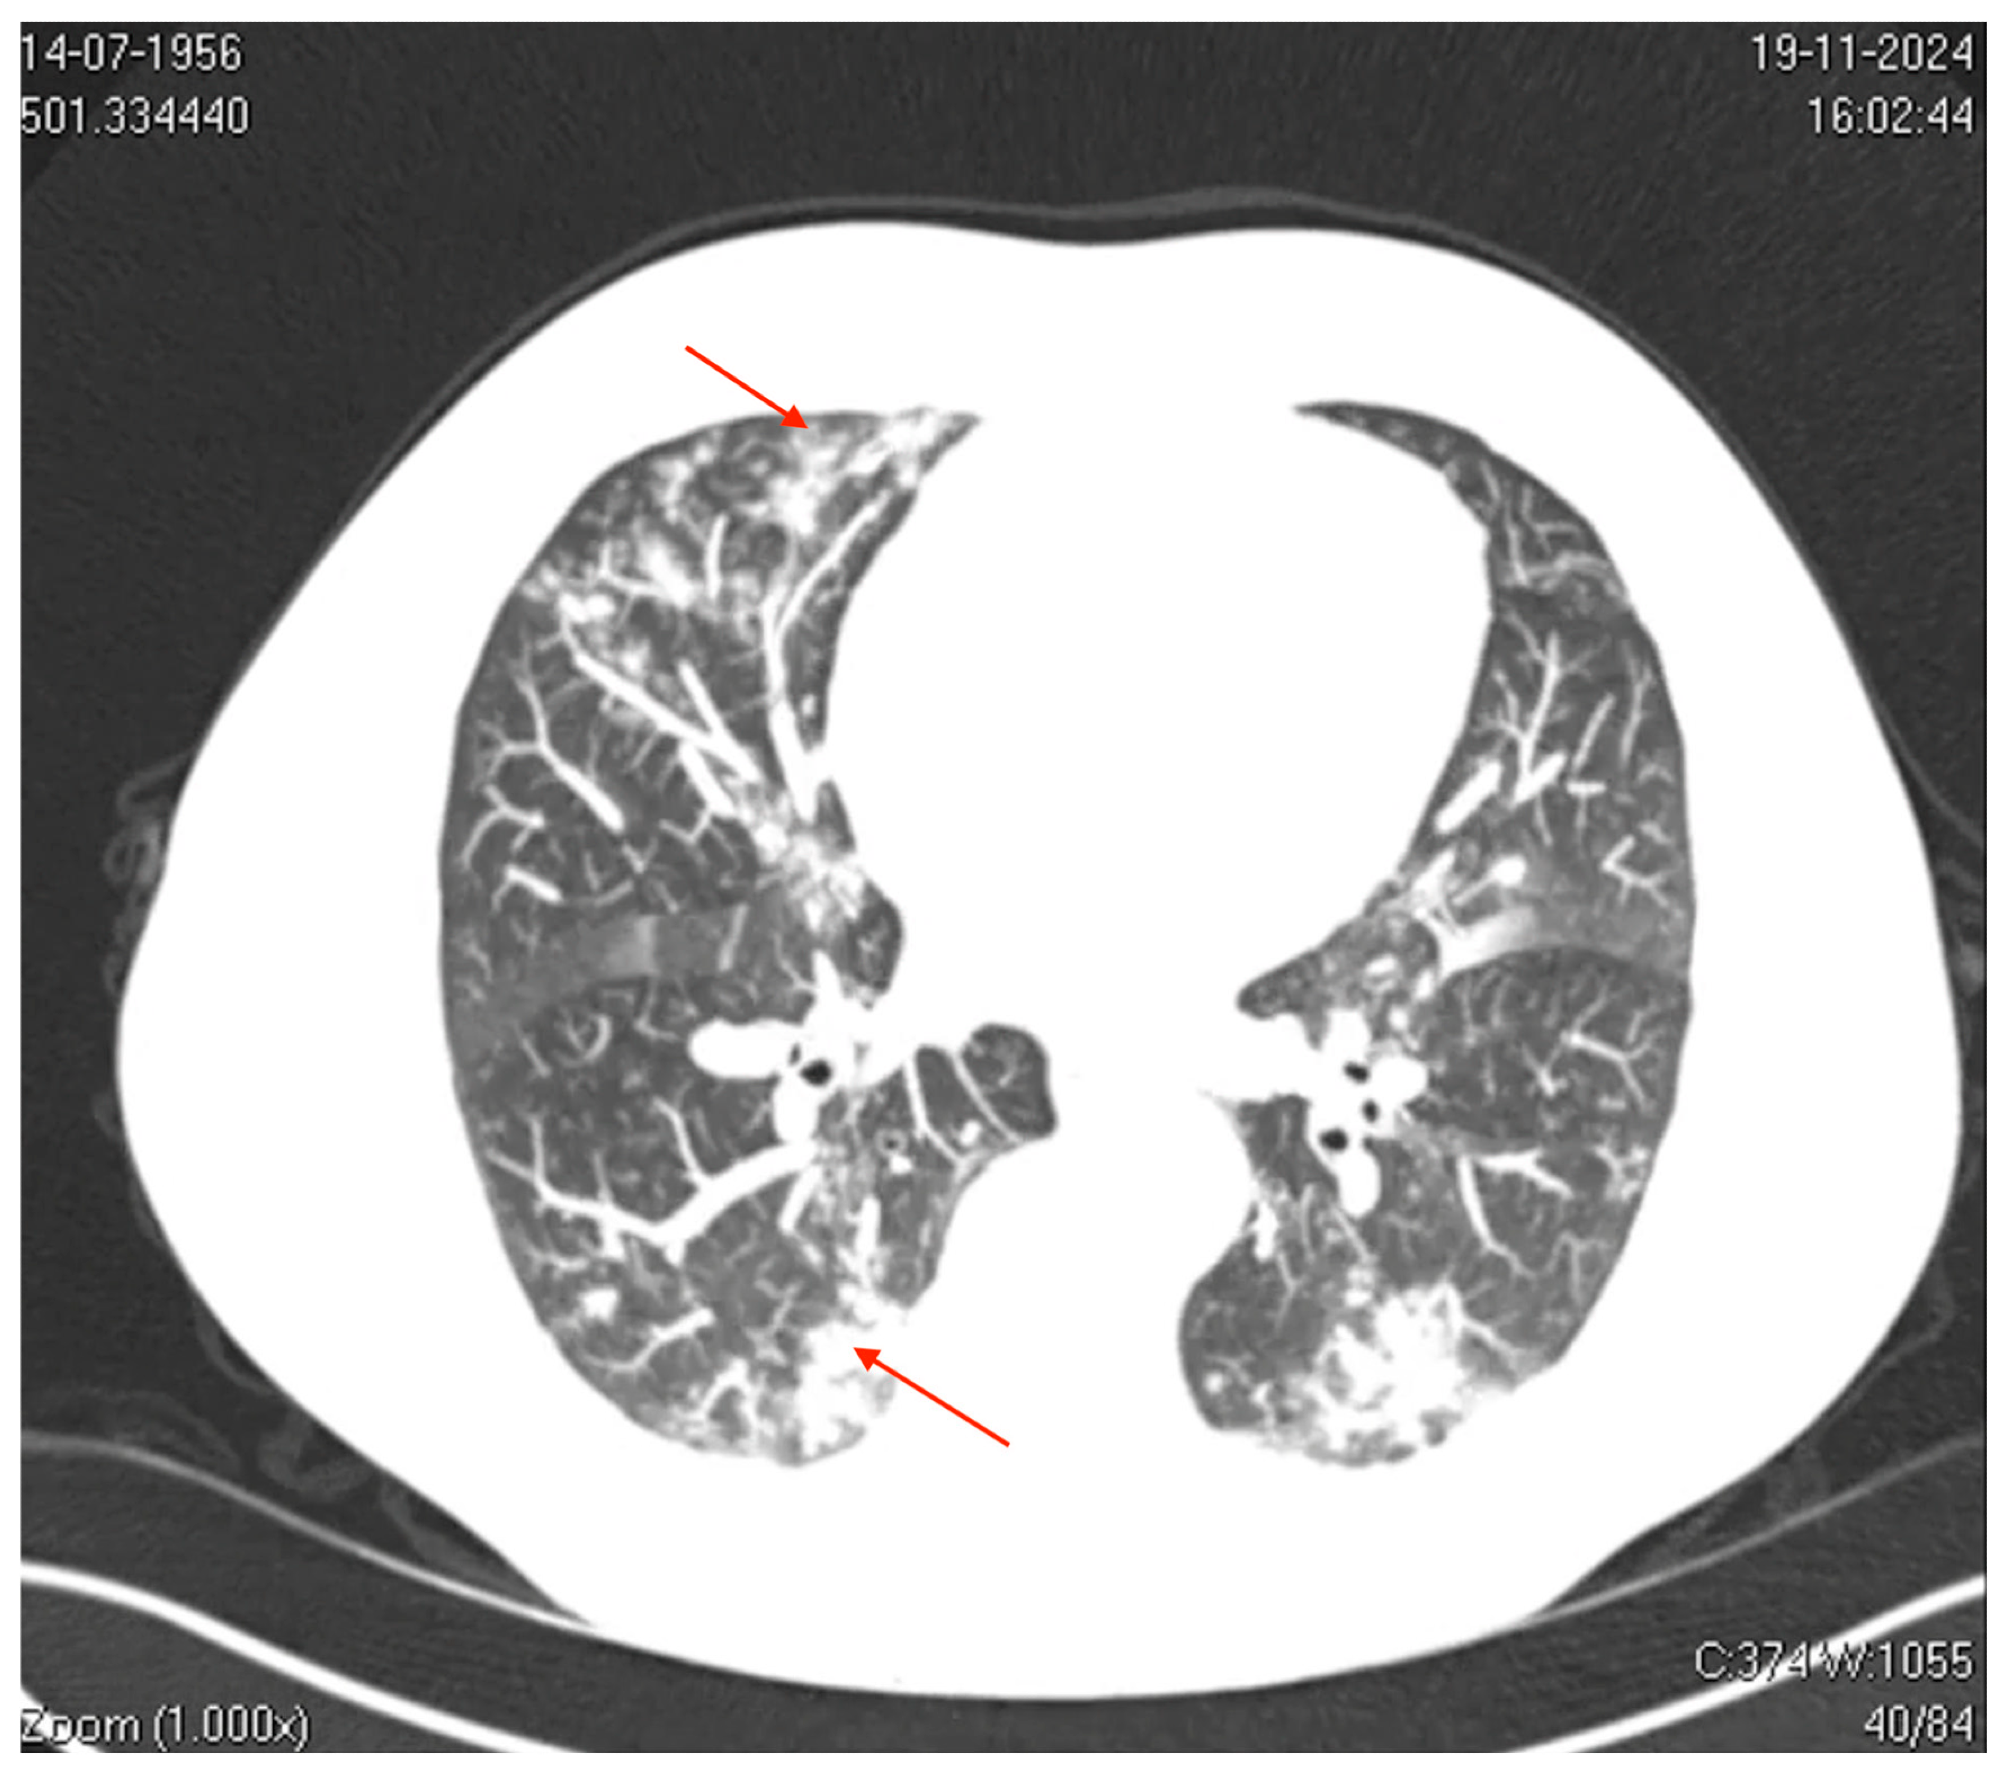

Axial computed tomography (CT) image of the thorax. The image shows bilateral ground-glass opacities with a reticular pattern interspersed with focal areas of consolidation and peripheral bronchiolar filling. The red arrows highlight specific areas of consolidation surrounded by ground-glass opacities, which are more prominent in the peripheral and lower lung regions. These findings suggest a diffuse inflammatory or infectious process involving the pulmonary interstitial and peripheral airways (acinus and bronchioles), which is consistent with viral pneumonia.

Nevertheless, the patient’s condition was exacerbated, with intense coughing, bronchospasm, myalgia, fatigue, and headache, prompting admission to the emergency department on D7. Laboratory findings revealed elevated inflammatory markers, including C-reactive protein (7.6 mg/dL) and D-dimer (870 ng/mL), thrombocytopenia, mild increase in transaminase, and normal procalcitonin and leucocyte levels, suggesting viral etiology. Imaging studies indicated significant pulmonary involvement.

Thoracic computed tomography (CT) showed mild bilateral pleural effusions, ground-glass opacities interspersed with areas of consolidation, and small centrilobular opacities. These findings were consistent with a viral pneumonia pattern and predominantly affected the left lower and upper lobes. Besides, CT of the paranasal sinuses revealed mucosal thickening in the frontal sinus.